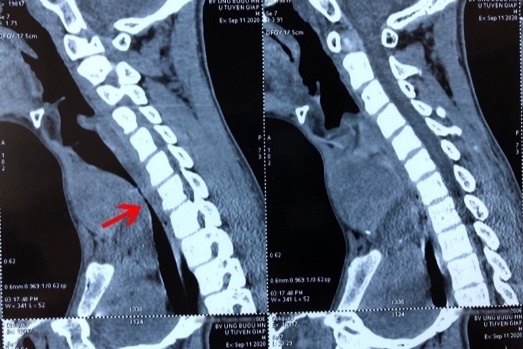

Các bác sĩ xác định khối u thùy giáp trái đã di căn phổi đa ổ, lan xuống hõm ức, kích thước 8x9 cm, đè ép khí quản lệch sang phải gây hẹp lòng khí quản.

Đường kính khí quản của bệnh nhi tại vị trí hẹp nhất chỉ còn 4 mm (với người bình thường là 12 mm). Đây cũng là nguyên nhân khiến A. khó thở nghiêm trọng. Ngoài ra, khối u còn khiến giọng nói của A. bị khàn, ăn uống khó khăn.

Hình ảnh khối u chèn ép gây hẹp lòng khí quản của bệnh nhi. Ảnh: BVCC.